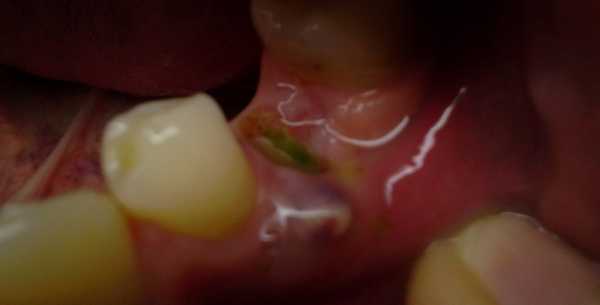

Кистой зуба называют новообразование (внешне похожее на мешочек или капсулу), покрытое фиброзной и эпителиальной тканью, внутри которого может находиться гной и отмершие клетки. Посмотрите на фото ниже, чтобы понять, как выглядит киста. Как правило, патология является следствием затяжного воспалительного процесса в полости рта: глубокого кариеса, запущенного пульпита, периодонтита. Для того, чтобы изолировать очаг инфекции, организм формирует защитную капсулу – кисту.

Так выглядит патология

Проблема этого заболевания заключается в том, что некоторое время, оно может никак себя не проявлять. Увидеть кисту при визуальном осмотре, можно лишь тогда, когда патологический процесс распространился на мягкие ткани. Посмотрев на фото кисты десны после неправильного удаления зуба, вы поймете, что не заметить ее невозможно. В иных случаях новообразование можно обнаружить лишь при помощи рентгена.

На фото показана киста, которая возникла после удаления зуба